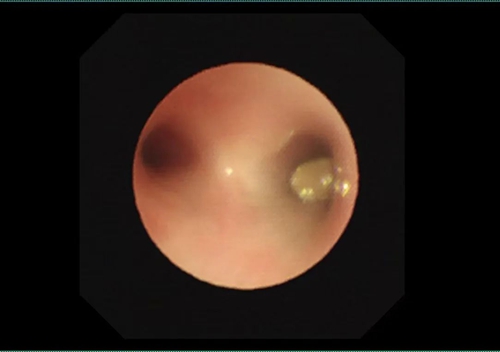

在醫(yī)生的再三追問下,家屬回憶起1個月前優(yōu)優(yōu)曾在家中進(jìn)食花生米后哇哇大哭,當(dāng)時查看并未發(fā)現(xiàn)嘴里有異物。醫(yī)護(hù)人員立即開通綠色通道,將優(yōu)優(yōu)收入呼吸二科病房住院治療。副主任醫(yī)師范文文接診后立即進(jìn)行異物取出術(shù),術(shù)中探查發(fā)現(xiàn)患兒右主支氣管管腔幾乎被異物完全阻塞。

呼吸二科團(tuán)隊與內(nèi)鏡中心團(tuán)隊緊密配合,最終順利取出半粒花生米,患兒管腔隨即恢復(fù)通暢。